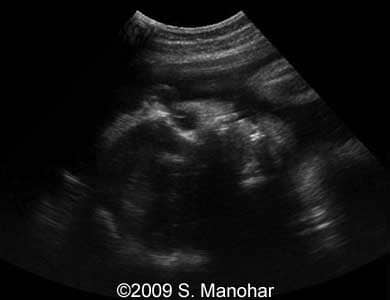

Images 3, 4: The image 3 shows a sagittal scan of the fetal head with protruding tongue (left part of the image). The right part of the image 3 and the image 4 represent a coronal scan at the level of the fetal lips, which are turned outward (so called "eclabion"). Hyperechoic incisor teeth can be seen in the opened mouth.

3

7